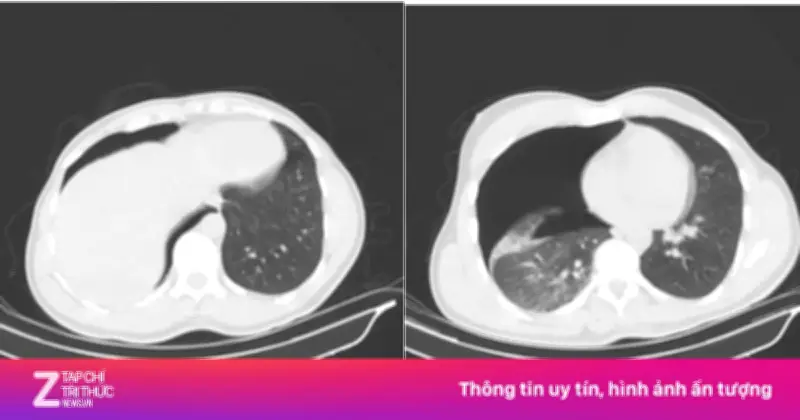

Kết quả chụp CT scan lồng ngực - mạch máu cho thấy bệnh nhân bị tràn khí màng phổi phải lượng nhiều, gây chèn ép phổi và khó thở. Ngoài ra, anh còn bị gãy cung bên các xương sườn số 2, 3, 4 bên phải và gãy phức tạp 1/3 giữa xương đòn phải với di lệch nhiều và có mảnh rời. Bác sĩ Phạm Ngọc Huy, thuộc khoa Điều trị theo yêu cầu - Y học thể thao, nhấn mạnh: "Nếu không can thiệp kịp thời, tình trạng suy hô hấp có thể diễn tiến nguy hiểm".

Vào khoảng 5 giờ sáng cùng ngày, ê-kíp khoa Phẫu thuật Tim - Lồng ngực - Mạch máu đã tiến hành đặt dẫn lưu màng phổi phải cấp cứu. Thủ thuật được thực hiện nhanh chóng và chính xác, giúp phổi nở trở lại tốt. Chỉ sau vài giờ, tình trạng hô hấp của bệnh nhân đã cải thiện rõ rệt, đánh dấu bước đầu thành công trong quá trình điều trị.